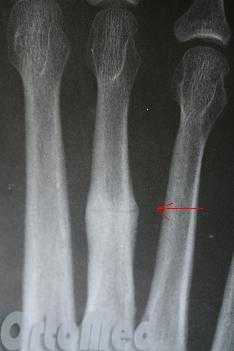

Переломы пальцев стопы

Обычно переломы пальцев возникают вследствие падения тяжелых предметов, поэтому нередко бывают открытыми либо сопровождаются выраженной травмой мягких тканей. Повреждения диафиза легко распознаются: появляется кровоизлияние, отек и боль, нарушается функция, отмечается положительный симптом осевой нагрузки. При эпифизеолизах без смещения симптомы могут напоминать ушиб, при эпифизеолизах со смещением – вывих фаланги. Диагноз помогает установить рентгенография.

Переломы фаланг пальцев стопы

Эта разновидность переломов костей стопы, как правило, возникает при прямом воздействии травмирующей силы (падение тяжести, удар по пальцам). Переломы средней и ногтевой фаланг пальцев в последующем не нарушают функцию стопы. Неправильное сращение переломов основных фаланг может приводить к развитию посттравматических артрозов плюснефаланговых суставов, ограничению подвижности и болям при ходьбе.

Травмированный палец синюшен, отечен, резко болезненен при движениях, ощупывании и осевой нагрузке. Переломы ногтевой фаланги часто сопровождаются образованием подногтевой гематомы. Для подтверждения переломов фаланг выполняют рентгенограммы в 2-х проекциях.